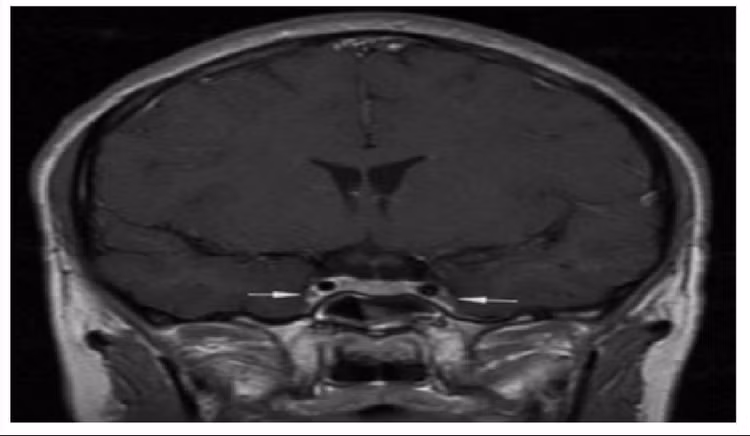

xoang-hang.jpg

Vị trí mũi tên là viêm và co thắt động mạch cảnh trong 2 bên - Ảnh BVCC